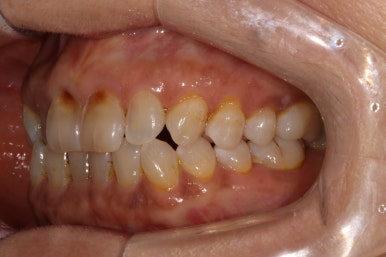

앞니의 치경부 마모가 눈에 띄긴 하지만, 전체적으로 쌓여있는 치석말고는 별 문제가 없었습니다.

화살표로 가리치고 있는 치아의 불편감을 호소하고 계셨습니다.

보시다시피, 아래턱 큰어금니의 씹는면에 약간의 충치가 있는바.. 일단 레진으로 떼우기로 치료계획을 세웠었죠.